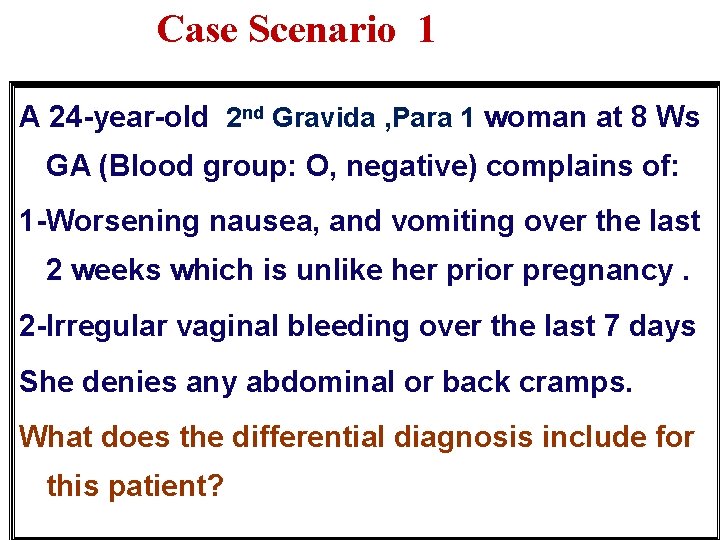

Case Scenario 1 A 24 -year-old 2 nd Gravida , Para 1 woman at 8 Ws GA (Blood group: O, negative) complains of: 1 -Worsening nausea, and vomiting over the last 2 weeks which is unlike her prior pregnancy. 2 -Irregular vaginal bleeding over the last 7 days She denies any abdominal or back cramps. What does the differential diagnosis include for this patient?

What Does The Differential Diagnosis Include For This Patient? The differential diagnosis of bleeding with early pregnancy and progressive vomiting are: Multiple pregnancy. Hydatidiform mole. Threatened abortion. Ectopic pregnancy.